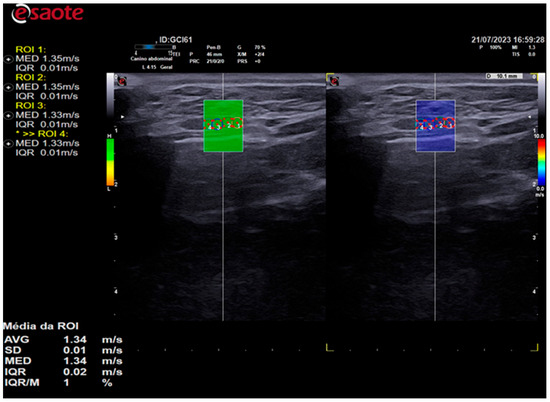

Elastographic images were obtained in the longitudinal plane of each thyroid lobe, and a scale of 0.0 to 10.0 m/s was employed in all cases. Once the thyroid lobe was properly framed in the image, the QelaXtoTM 2D software quality map was initiated. The map indicated the most suitable locations for acquiring shear-wave velocity. These were colored green to indicate high quality (Figure 3), yellow to indicate medium quality, and orange to indicate low quality (Figure 4).

Figure 3. The image on the left is a 2D shear-wave elastography image of the left thyroid lobe of a 10-year-old dog. The elastographic image on the left shows a quality map from the QelaXtoTM 2D software, which is colored green. This indicates that the image is of high quality for measuring shear-wave velocity, which is a quantitative measurement. The right side of the elastographic image displays the colored elastogram (qualitative) from the QelaXtoTM 2D software in blue, indicating that the thyroid parenchyma had low stiffness (soft).